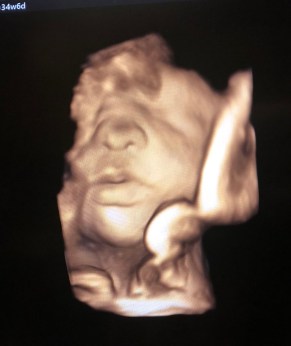

The doctors diagnosed Kenji at 18 weeks of gestation. For my husband and I it was very hard because we did not know anything about Spina Bifida. Many bad thoughts came to our heads about what Kenji’s life would be like. The doctors offered to abort but I said I was not going to stop the pregnancy, that I was going to have him as God intended and love him as he was.

When Kenji was born he was beautiful! He was immediately taken to intensive care. He was born at 2 in the afternoon of January 9, 2018, and at 7 o’clock the next morning he was being operated on for 9 hours. My little one fought! Surgery went very well. We spent 10 days in Tufts. In those days I did not leave his side for a moment. Next, they had to operate on his head because he still had fluid on his brain. He was sent to the Children’s Hospital with Dr. Benjamin Warf. God is so big that when Kenji arrived for that surgery they decided not to operate because the fluid was decreasing. Instead, they kept him for observation for 3 days to repeat the study. When they did the study again it was better than the previous ones.